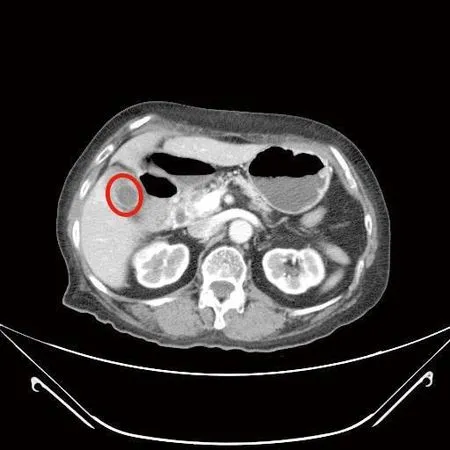

▲婦人同時有胃腸道基質瘤與膽囊炎,紅圈處為膽囊炎。(圖/國泰醫院提供)

72歲林女士,3年前經上消化道內視鏡檢查發現有個2公分大的胃黏膜下腫瘤,疑似胃腸道基質瘤,持續門診追蹤,近期發現腫瘤緩慢長大,2個月前因上腹部悶痛且頭暈就診,由於合併有血便症狀,經上消化道內視鏡及電腦斷層檢查,發現腫瘤已接近6公分大,同時膽囊被結石塞滿,已經沒有膽汁的空間,最後透過微創手術進行部分胃切除以及膽囊切除,一次完成治療。

由於術後僅1個3-5公分及3-4個1公分傷口,大幅降低病人術後傷口疼痛感,患者術後第9天出院。病理化驗報告證實胃部腫瘤屬於低度分化惡性胃腸道基質瘤,評估後僅需定期追蹤檢查,膽囊則是慢性膽炎。